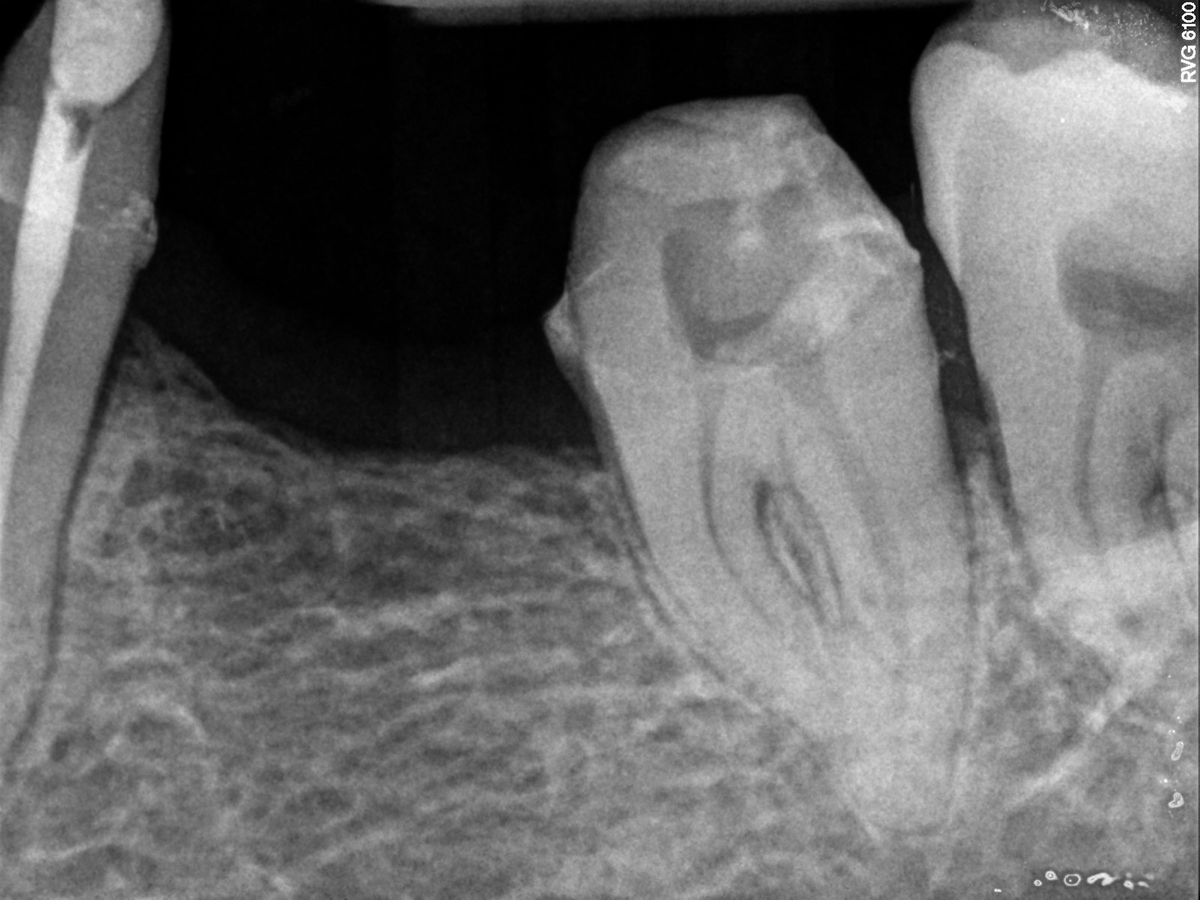

Pre trattamento

Il granuloma normalmente è ben visibile con piccole radiografie endorali (link) in cui si vedrà un’area più scura di rarefazione ossea intorno all’apice di una o più radici. Con il tempo, e senza trattamento, il suo volume si estenderà fino a rompere la corticale ossea più esterna e questo comporterà la formazione di un’ascesso. L’andamento cronico e silenzioso della lesione può essere quindi interrotto da improvvisi e dolorosi episodi ascessuali.